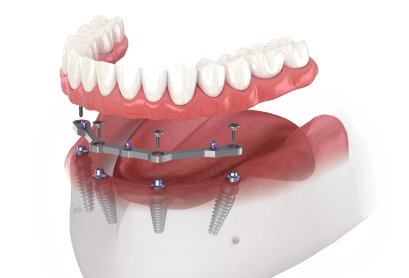

Full-arch dental implant treatment is a complex process that requires careful evaluation and planning. It is essential to consult with our dentist, Dr. LaKendra Sakeena, to determine if full-arch dental implants are the right option for you and to discuss the specific treatment details, expected outcomes and potential risks. If you have any questions about full-arch dental implants in Missouri City, Texas, we invite you to call Sienna Smiles at 281-778-3200 today.

Be free to smile, eat and speak with full-arch dental implants